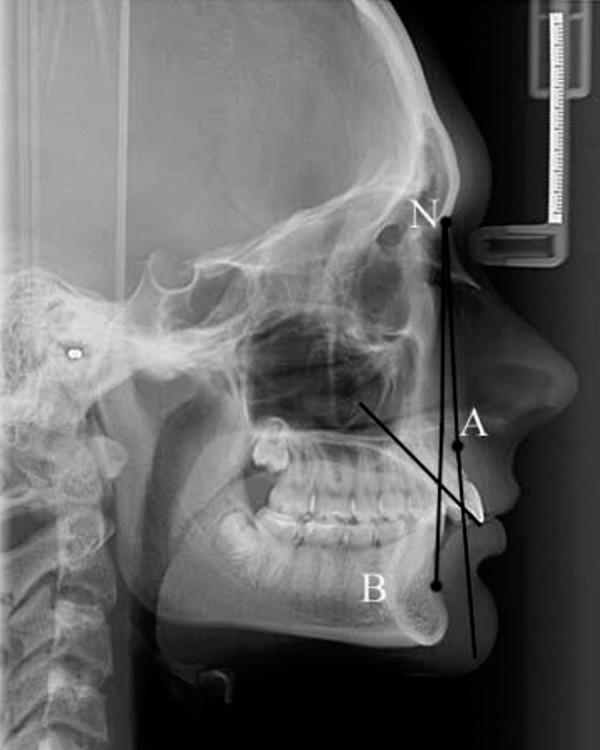

Male and Female Characteristics of Facial Soft Tissue Thickness in Different Orthodontic Malocclusions Evaluated by Cephalometric Radiography.

BACKGROUND The facial profile is determined by the facial soft tissue thickness (FSTT) and dentoskeletal characteristics. The aim of this study was to compare male and female characteristics of FSTT in different orthodontic malocclusions using cephalometric radiography. MATERIAL AND METHODS One hundred and twenty lateral cephalometric radiography-derived cephalograms of adult male (n=47) and female (n=73) orthodontic patients, aged between 16-22 years were classified according to their dentoskeletal relationships as Class I (n=30), Class II Division 1 (n=30), Class II Division 2 (n=30), Class III (n=30). Burstone analysis of seven linear dimensions of FSTT was used. RESULTS Men had a thicker FSTT in dentoskeletal relationships Class I, Class II Division 2, and Class III. Sex differences varied from significant (t=2.056; p<0.05) for the sub-nasal area in Class II Division 2, to highly significant (t=3.772; p<0.001) for the upper lip sulcus in Class II Division 2. Women in Class II Division 1 had significantly thicker FSTT in the lower jaw area (t=2.800; p<0.01) and for the lower lip sulcus and the chin area (t=3.961; p<0.001). CONCLUSIONS Men with orthodontic malocclusions were characterized by thicker facial soft tissue compared with female patients in Class I and Class II Division 2; female patients in Class II Division 1 were characterized by thicker facial soft tissue of the mentolabial sulcus and chin. Men and women with a skeletal jaw relationship in Class III showed no significant difference in their FSTT.

将 120 例年龄在 16-22 岁的成年男性(n=47)和女性(n=73)正畸患者的头颅侧位片分为骨性 I 类(n=30)、安氏Ⅱ类 1 分类(n=30)、安氏Ⅱ类 2 分类(n=30)、安氏Ⅲ类(n=30)。采用 Burstone 分析法测量 FSTT 的 7 项线性指标。